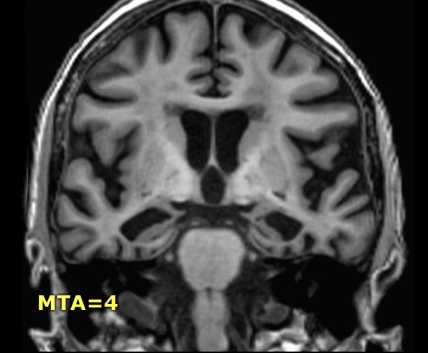

Patient in Dementia. Get link Facebook X Pinterest Email Other Apps - March 22, 2020 Reference Get link Facebook X Pinterest Email Other Apps Comments